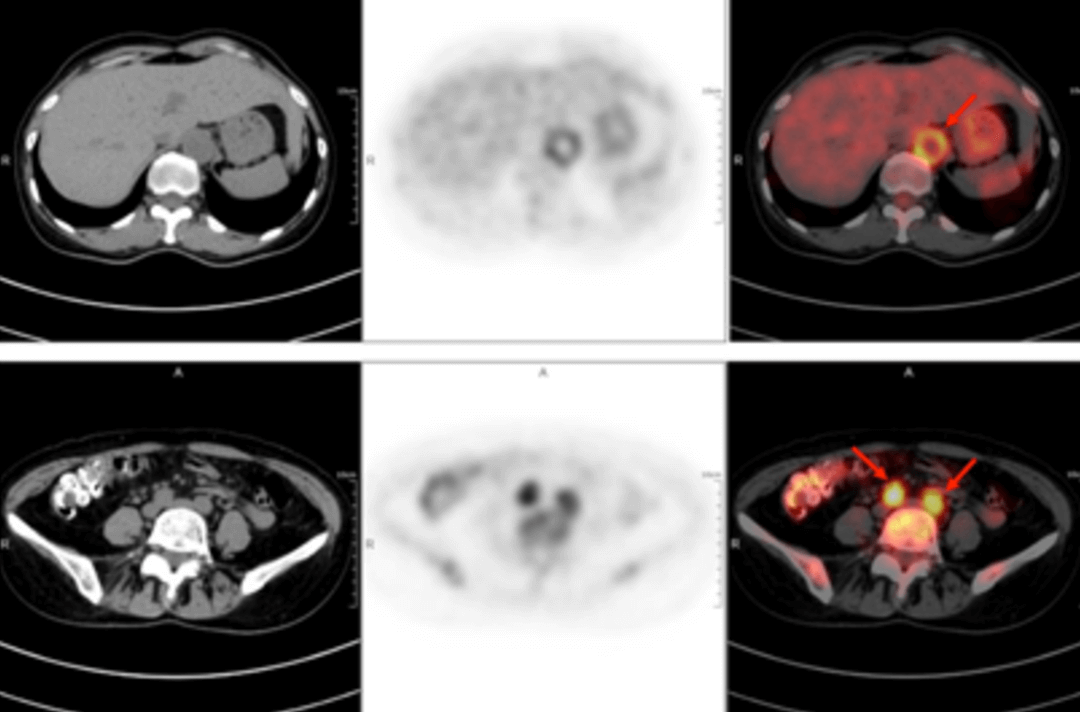

58-letnia kobieta trafiła do szpitala z powodu gorączki trwającej z przerwami od ponad 40 dni. Najwyższa zmierzona temperatura ciała wynosiła 38,9℃. Inne objawy obejmowały zmęczenie i ból stawów barkowych szczególnie nasilony po południu oraz nocą, dreszcze, krwioplucie, ból i ucisk w klatce piersiowej oraz duszności. Po dwóch tygodniach dożylnego podawania antybiotyków cefalosporynowych nie było poprawy, a gorączka się utrzymywała. W poradniach odnotowywano u pacjentki „gorączkę nieznanego pochodzenia”. W badaniu przedmiotowym nie znaleziono ewidentnych wskazówek pozwalających na diagnozę. Wyniki rutynowego badania krwi były następujące: wskaźnik sedymentacji erytrocytów w pierwszej godzinie – 72 mm; białko C-reaktywne o wysokiej czułości: 204,20 mg/l. Następnie u chorej wykonano badanie PET/TK całego ciała z zastosowaniem znacznika F-FDG (fluorodeoksyglukozy) w celu znalezienia przyczyny gorączki nieznanego pochodzenia.

W obrazach PET/TK w kilku lokalizacjach (obustronna tętnica szyjna wewnętrzna, tętnica szyjna wspólna, pień ramienno-głowowy, obustronne tętnice podobojczykowe i pachowe, aorta piersiowa, aorta brzuszna, obustronna tętnica biodrowa wspólna, tętnica biodrowa wewnętrzna, tętnica biodrowa zewnętrzna i tętnica udowa) wystąpiło pogrubienie ściany ze zwiększonym metabolizmem glukozy, co uznano za spowodowane zmianami zapalnymi. Na podstawie wywiadu lekarskiego, objawów klinicznych, badania i wyników badań obrazowych u pacjentki rozpoznano zespół Takayasu. Po zastosowaniu standardowego leczenia przeciwzapalnego temperatura ciała spadła, a stan pacjentki uległ poprawie.